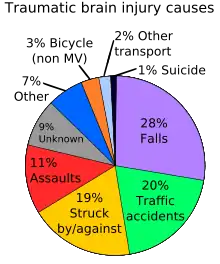

Traumatic brain injury (TBI) often occurs from damage to the brain caused by an outside force, and may lead to cases of amnesia depending on the severity of the injury.[8] Head injury can give rise to either transient or persisting amnesia. Occasionally, post-traumatic amnesia (PTA) may exist without any retrograde amnesia (RA), but this is often more common in cases of penetrating lesions. Damage to the frontal or anterior temporal regions have been described to be associated with disproportionate RA. Studies have illustrated that during PTA, head injury patients showed accelerated forgetting of learned information. On the other hand, after PTA, forgetting rates were normal.[8]

As noted in the above-mentioned section on traumatic brain injury it can be associated with memory impairment, Alzheimer's disease; however, as far as aging is concerned it poses other threats as well. There is evidence that supports a high incidence of falls among the elderly population and this is a leading cause of TBI-associated death among the population of people 75 years of age and older.[9] When looking at the chart to the right on the page, it states that falls are only 28% of the total causes of TBI, so that would suggest that the elderly make up a good portion of that 28% overall. Another factor associated with TBI and age is the relationship between when the injury was sustained and the age at which it occurred. It is estimated that the older the individual, the more likely they would require assistance post TBI.[9]